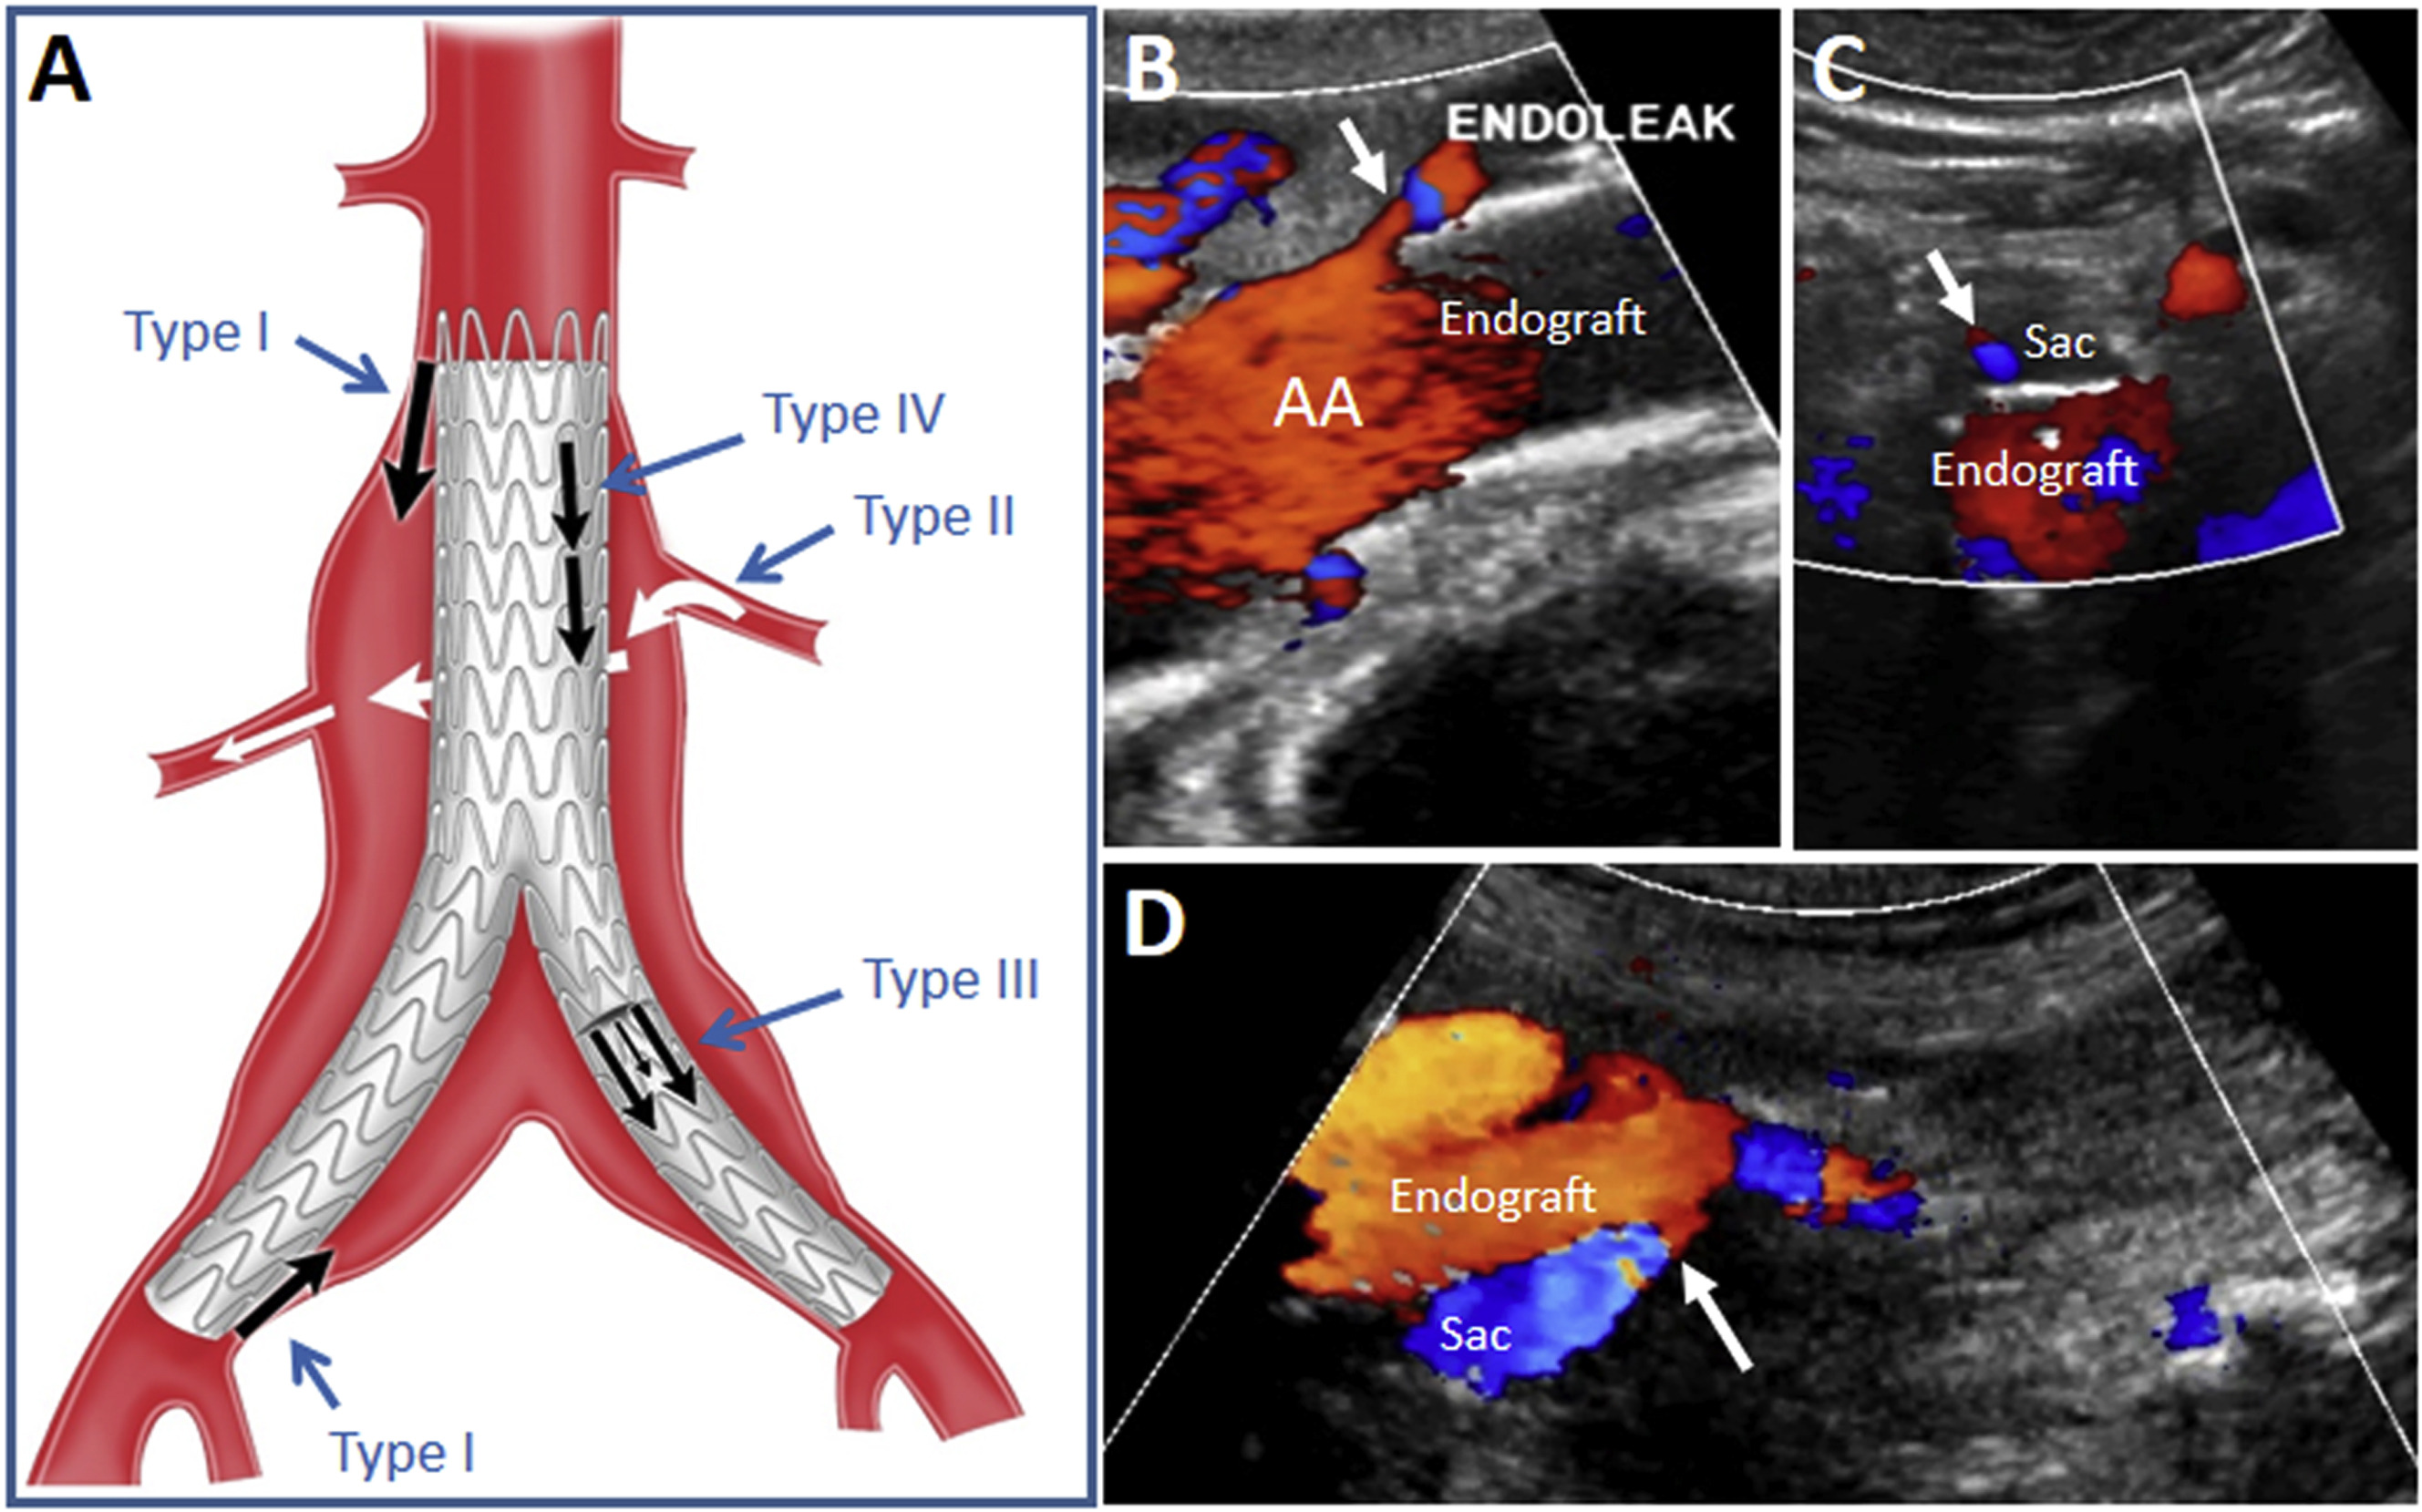

복부 대동맥류(AAA)

- 직경 3 cm 이상, 또는 정상 대비 50% 이상 확장된 상태를 말합니다.

- 5.5 cm 이상이면 파열 위험이 급격히 증가하므로 수술·스텐트 삽입을 검토합니다.

- ≥ 5.5 cm: 수술·EVAR(혈관 내 스텐트) 적극 고려.